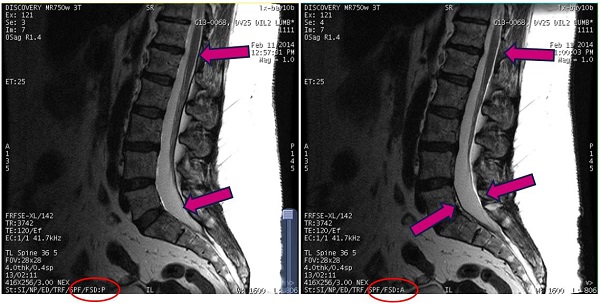

| Image | Description |

|---|---|

| Left | Fat Shift Direction set to Normal. |

| Right | Fat Shift Direction set to Reversed. |

The fat direction is annotated in the lower left corner of the image as FSD:X where X indicates the direction: A (anterior), P (posterior), R (right), L (left), S (superior), I (inferior).